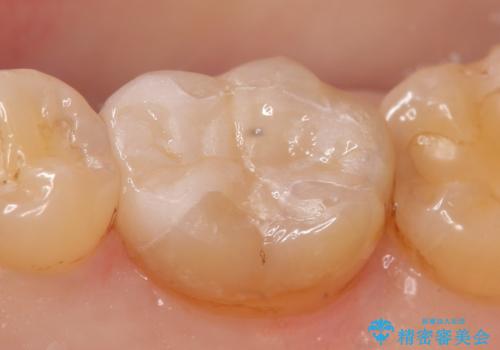

50代女性 骨が無い→ショートインプラントで咬み合わせを回復②

インプラントの2次ope時に歯ぐきの移植をおこない、インプラントがより長く機能する環境づくりをします。バイコンインプラントに特有のシステムにて被せものを製作します。

不安定だった左の咬み合わせをしっかりと機能させることができました。

インプラントの種類:Bicon

被せものの種類:高透過フルジルコニア ベレッツァ